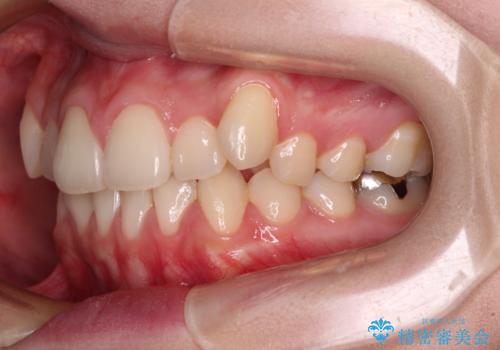

- 左右の八重歯を気にして来院された患者様です。

歯列としてはインビザラインでもワイヤー矯正でも対応できるものでしたが、インビザラインによる治療を希望されていました。

上顎の八重歯改善にインビザラインでは時間のかかってしまう可能性があり、更には口元が治療前よりも突出してしまう可能性があったため、補助装置により八重歯を事前に引き込んでおくことで、インビザラインによる治療をスムーズに行えるように計画しました。